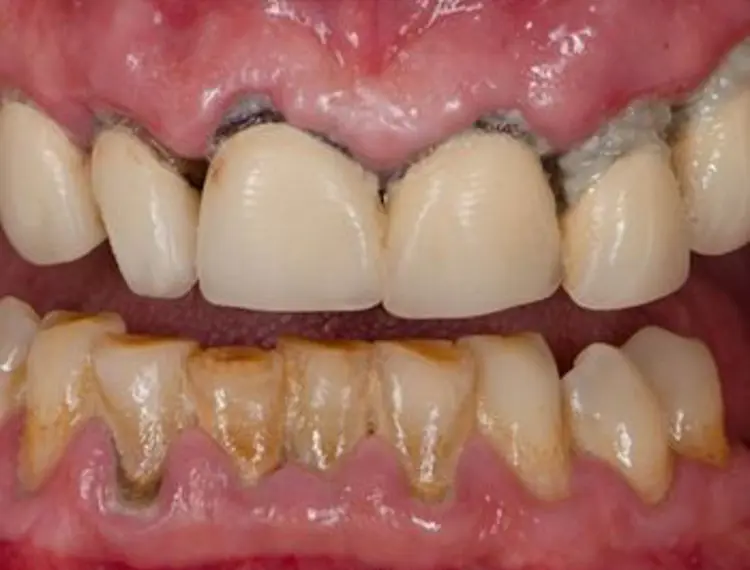

Periodontitis is caused by damaging bacteria that can cause damage to the gums and bone that support the teeth. (Figure 1C-Figure 1D). This causes pockets of space under the gums around the teeth.

- gums pull back making the teeth look longer